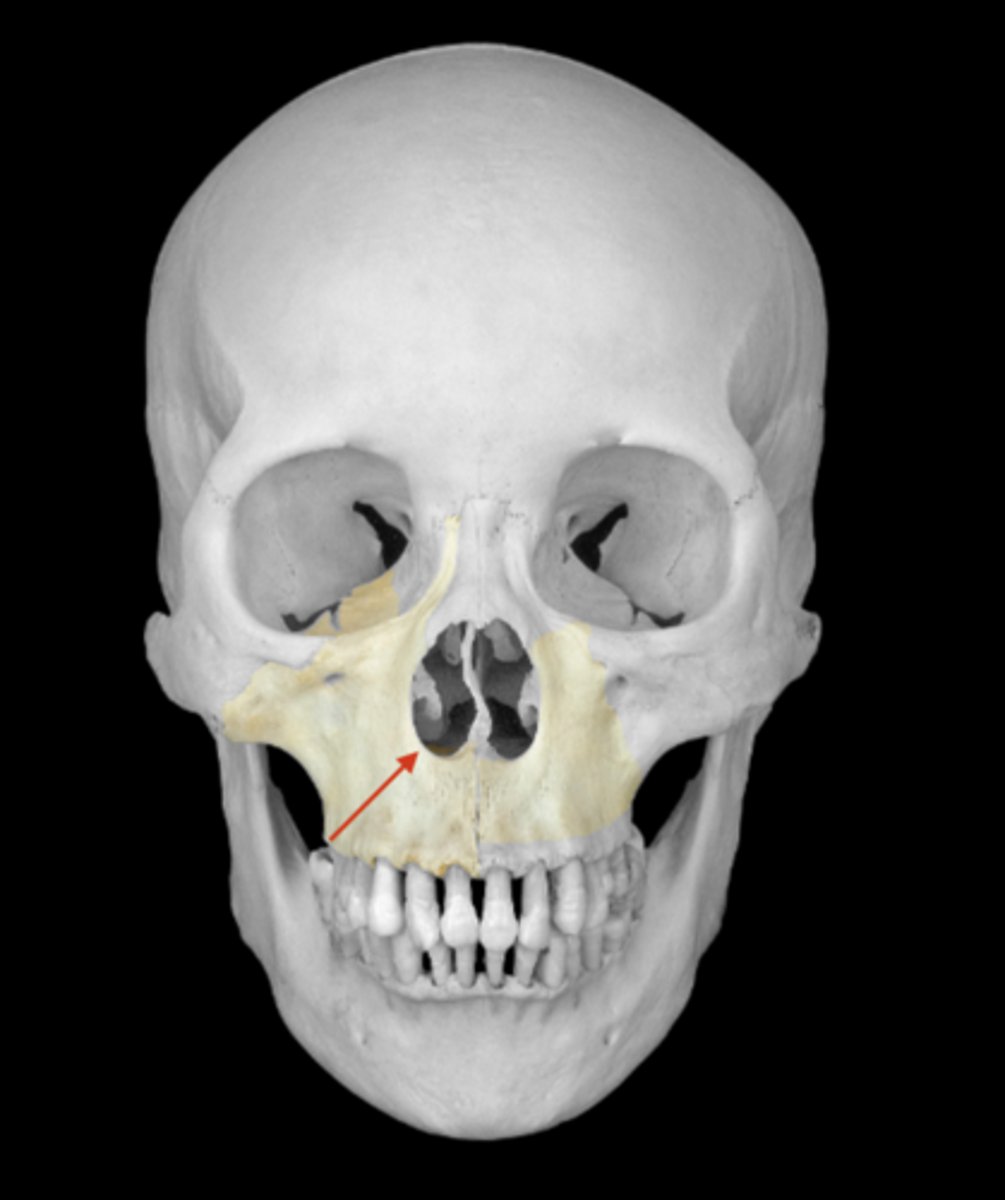

maxilla bone

nasal aperture of maxillae

frontal process of the maxilla

orbital surface of the maxilla

infraorbital margin of the maxilla

infraorbital foramen of maxilla

anterior nasal spine of maxilla

maxillary sinus of maxilla

lacrimal groove of maxilla

anterior lacrimal crest of maxilla